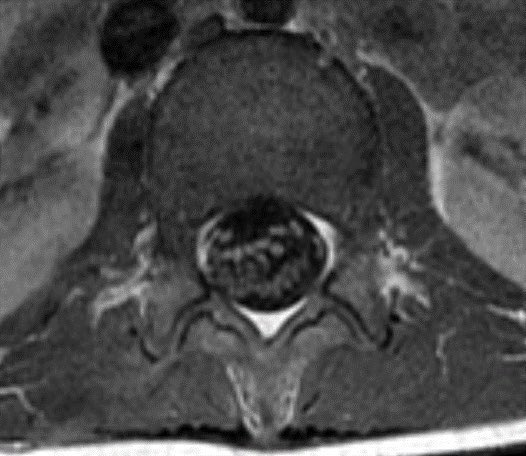

@mskteachingroom @mskradiologyuk @SidThakerMSK @jacja_ @veronica_giotas @PrimeFellowship Migrations of Ca tendinopathy

Spot Diagnosis?